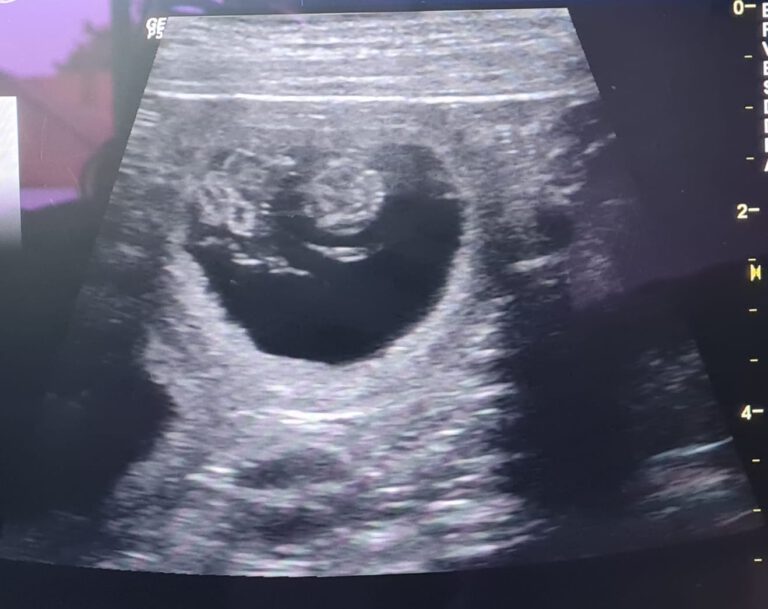

Die Gebärmutter zeigt zunächst oviole Fruchtampullen , die um den 33. bis 35. Tag ”zusammenfließen”…

WELPENALARM! Heute hat uns der Ultraschall bestätigt, was wir in der letzten Woche schon geahnt…

Am 25.09. + 26.09. wurde Didget hoffentlich erfolgreich gedeckt. Der Ultraschall wird uns Ende Oktober…